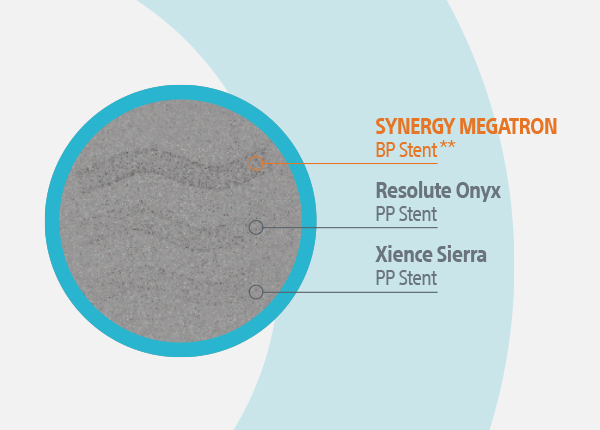

Medical Specialties > Interventional Cardiology > Coronary Interventions > PCI Product Portfolio > SYNERGY MEGATRON™